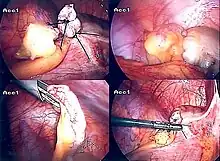

Surgery

The surgical procedure for the removal of the appendix is called an appendectomy. Appendectomy can be performed through open or laparoscopic surgery. Laparoscopic appendectomy has several advantages over open appendectomy as an intervention for acute appendicitis.[84]

Laparoscopic appendectomy

Laparoscopic appendectomy was introduced in 1983 and has become an increasingly prevalent intervention for acute appendicitis.[88] This surgical procedure consists of making three to four incisions in the abdomen, each 0.25 to 0.5 inches (6.4 to 12.7 mm) long. This type of appendectomy is made by inserting a special surgical tool called a laparoscope into one of the incisions. The laparoscope is connected to a monitor outside the person's body, and it is designed to help the surgeon to inspect the infected area in the abdomen. The other two incisions are made for the specific removal of the appendix by using surgical instruments. Laparoscopic surgery requires general anesthesia, and it can last up to two hours. Laparoscopic appendectomy has several advantages over open appendectomy, including a shorter post-operative recovery, less post-operative pain, and lower superficial surgical site infection rate. However, the occurrence of an intra-abdominal abscess is almost three times more prevalent in laparoscopic appendectomy than open appendectomy.[89]